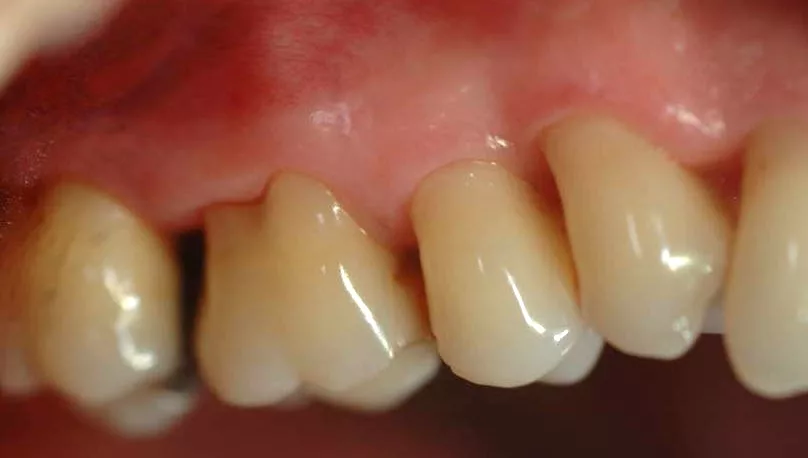

Face externe

Des techniques chirurgicales de préservation papillaire permettent de régénérer les tissus parodontaux en garantissant leur maintien esthétique. Ces techniques chirurgicales avancées s’effectuent sous aides optiques grossissantes et avec des instruments micro chirurgicaux spécifiques.